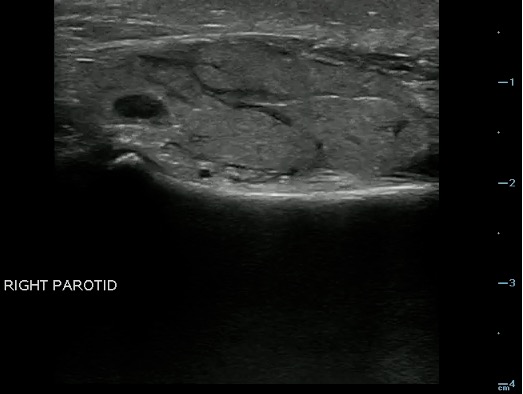

- Figure 19 and 20. Parotid gland lymph nodes

Video 14. Parotid gland lymph nodes

- The Parotid gland has intraglandular lymph nodes that are commonly seen within the parenchyma of the parotid gland.